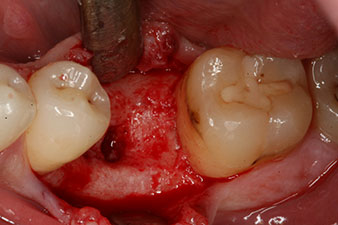

Fig. 1: Initial clinical situation after healing of extraction alveolus 36: The bone base is wide and there is sufficient keratinized gingiva.

A 28-year-old patient with a history of heavy smoking had to have tooth 36 extracted as a result of recurring apical periodontitis.

Due to the generally intact neighbouring teeth the only way to fill the gap was an implant.

Fig. 2: Six weeks later there was an incompletely ossified alveolus in the region of the mesial root.

However, six weeks after the extraction incomplete ossification was found after preparation of the mucoperiosteal flap in the region of the former mesial alveolus.